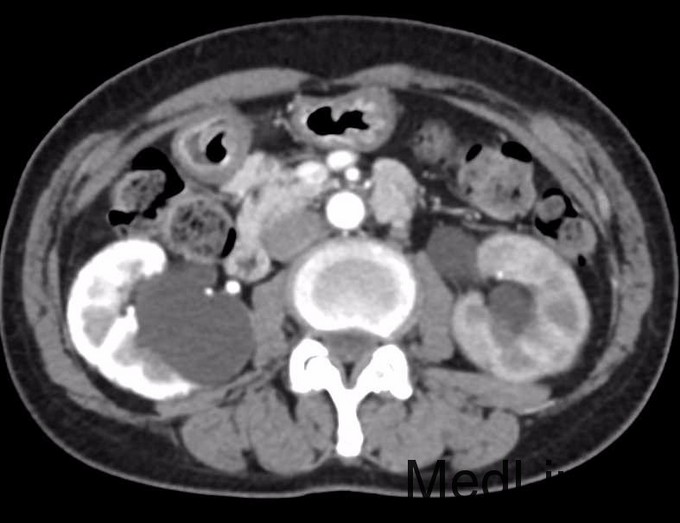

患者曾传华,女,65岁,主因左腰胀痛1月收入院。 患者1月前无明显诱因出现左腰部胀痛,阵发性发作,无尿频、尿急、尿痛,无恶心呕吐及发热。当地医院B超检查示左肾积水,遂至我院检查,CT(2015-9-30)示:左侧输尿管中段占位,考虑肿瘤性病变可能,继发左侧输尿管、肾盂肾盏扩张、积水。今为进一步诊治转来我院,今日收入院。

输尿管占位 输尿管镜取活检

这个病例上级大夫几乎认定是输尿管癌,已经准备做手术了,然而活检结果却显示慢性炎症!